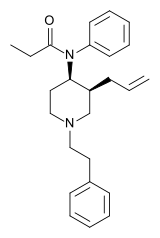

Anilidopiperidines

- 3-Allylfentanyl

- 3-Methylfentanyl

- 3-Methylthiofentanyl

- 4-Phenylfentanyl

- Alfentanil

- α-Methylacetylfentanyl

- α-Methylfentanyl

- α-Methylthiofentanyl

- Benzylfentanyl

- β-hydroxyfentanyl

- β-hydroxythiofentanyl

- β-Methylfentanyl

- Brifentanil

- Butyrfentanyl

- Carfentanil

- Fentanyl

- Lofentanil

- N-Methylcarfentanil

- Mirfentanil

- Ocfentanil

- Ohmefentanyl

- Parafluorofentanyl

- Phenaridine

- R-30490

- Remifentanil

- Sufentanil

- Thenylfentanyl

- Thiofentanyl

- Trefentanil

Structures